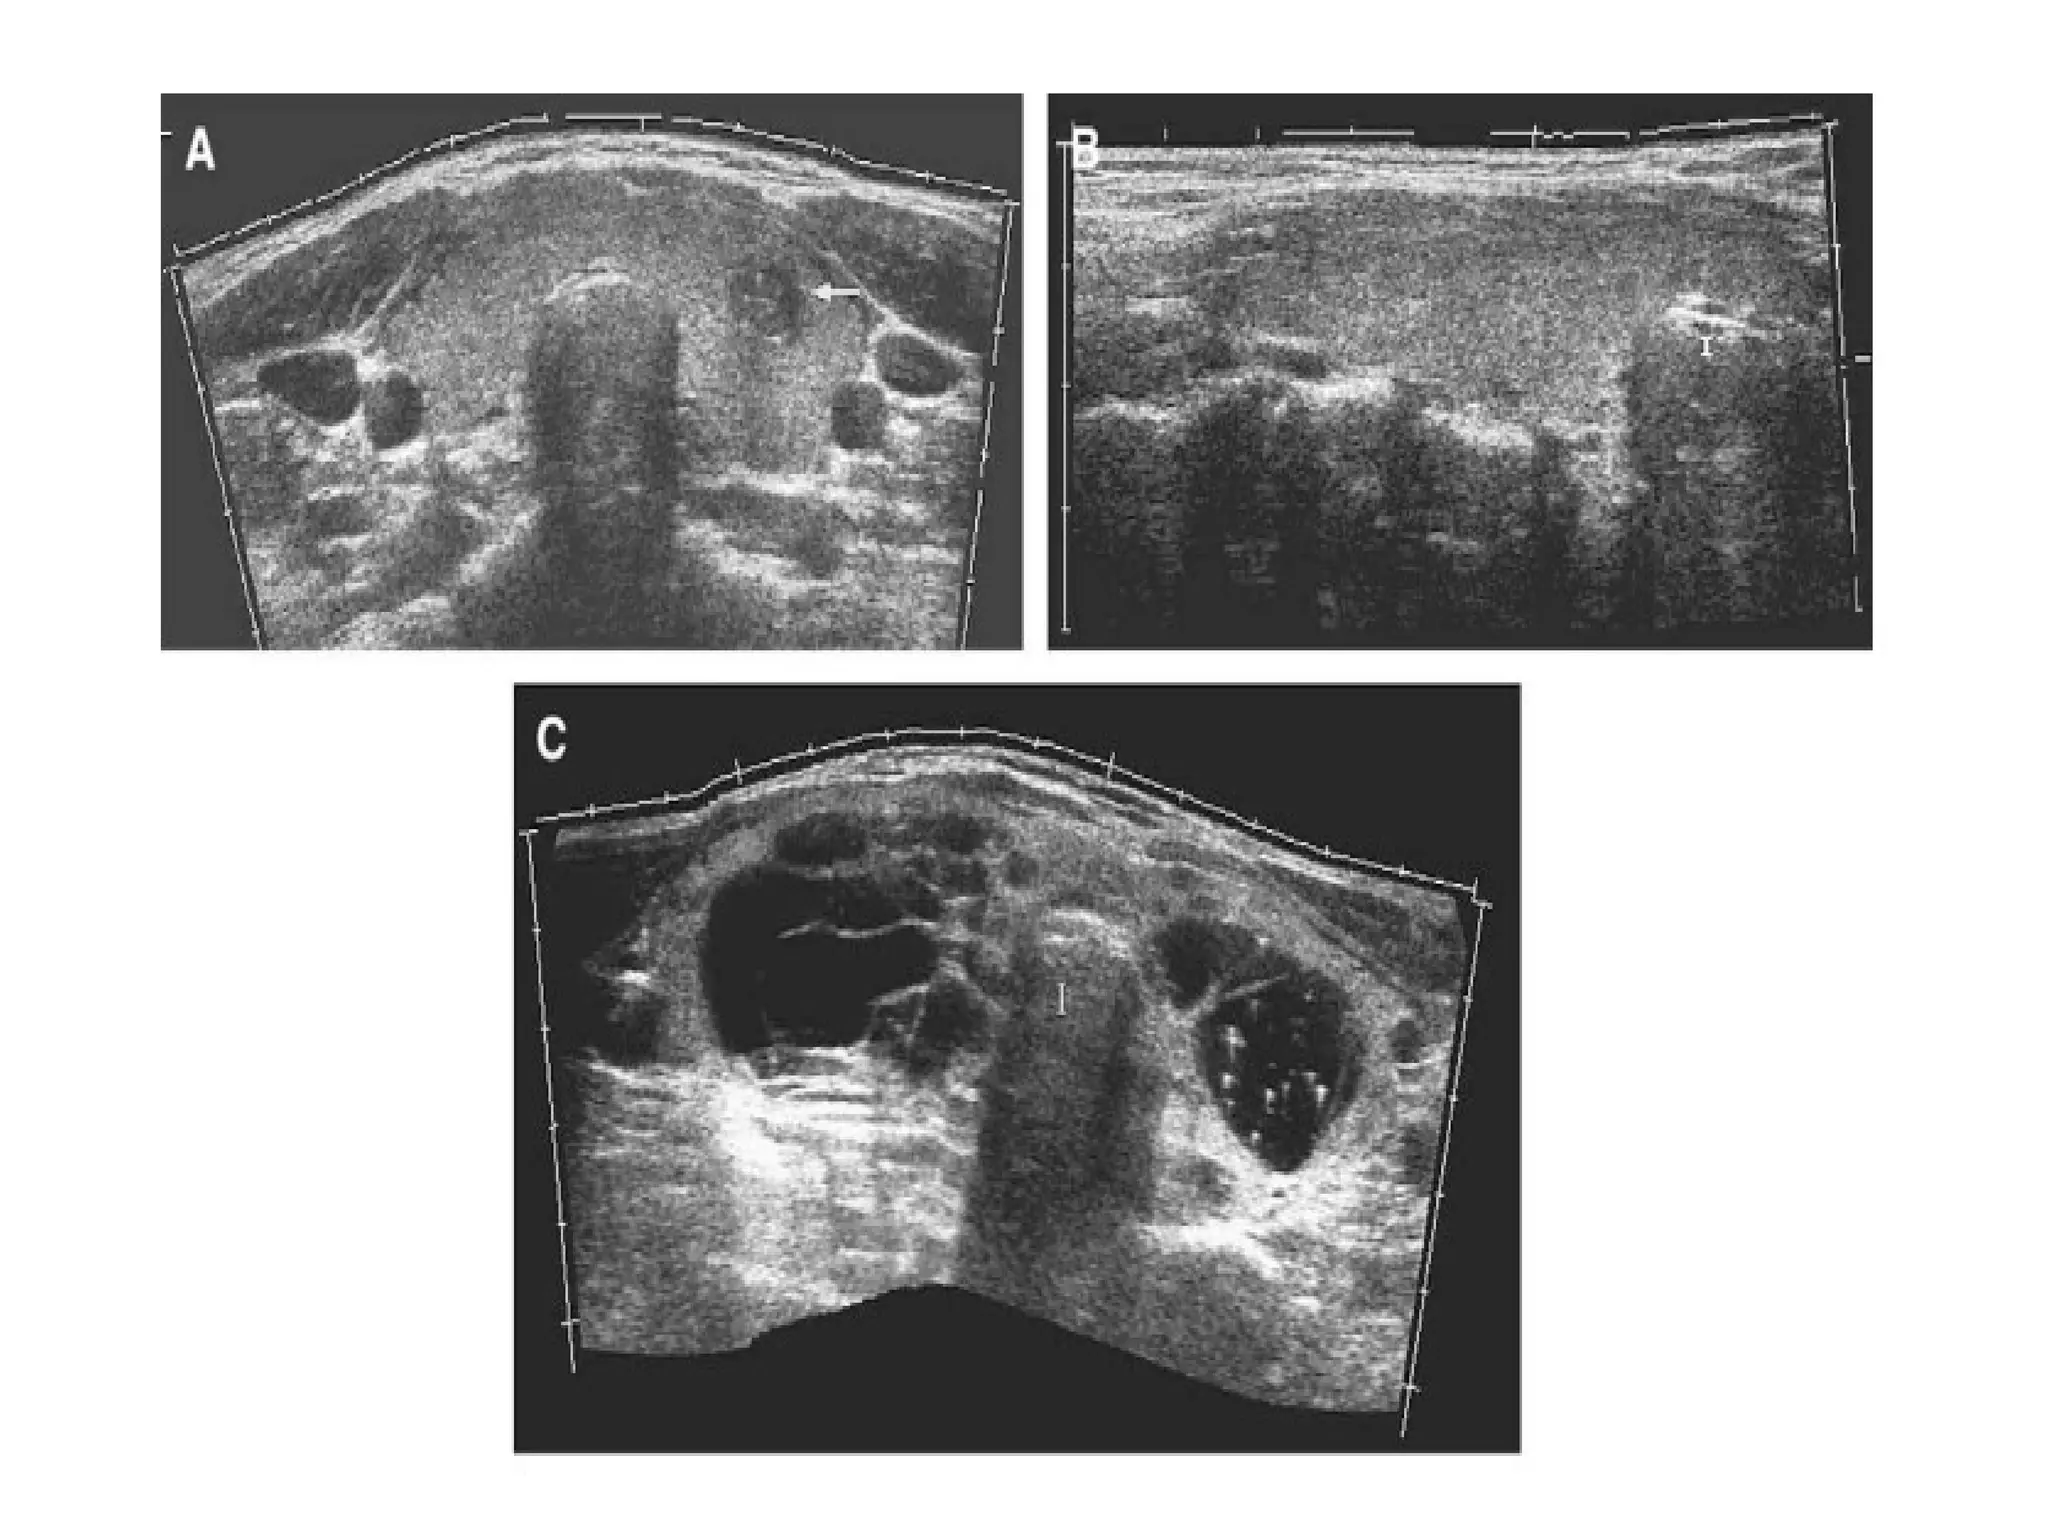

EXTENDED FIELD OF VIEW

• Allows sonologists to visualize large anatomic

regions in a single image.

• It can be performed with a linear array

transducer or using a curvilinear probe, although

most of its applications are in superficial

structures.

• It differs from traditional US by allowing global

depiction of an abnormality and its relation to

adjacent anatomic structures within a single

image.

• Transducer is initially moved laterally across

the anatomic area of interest and multiple

images are acquired from many transducer

positions.

• Images are registered with respect to each

other.

• This registered data is subsequently combined

to form one complete large field of view